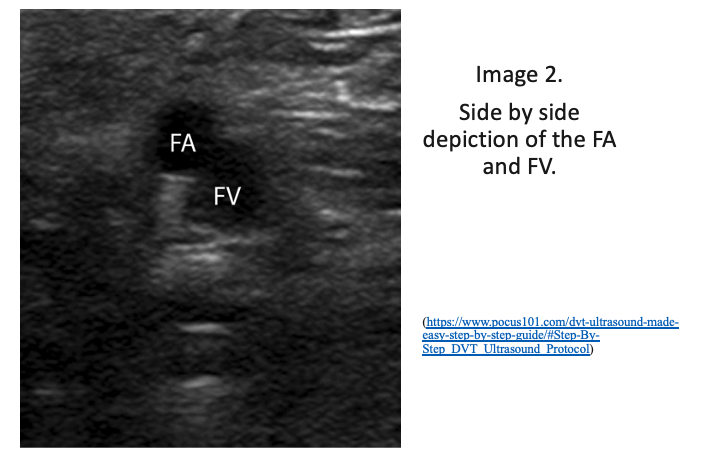

2. Continue to scan distally to locate where the CFV branches into the deep femoral vein and the femoral vein (previously known as superficial femoral vein). Remember the CFV will be medial to the common femoral artery. Compress the femoral vein distal to the bifurcation of the CFV at the SFJ. I like to compress until I cannot visualize anymore and the vasculature dives into the adductor canal.  Firmly compress the ultrasound probe to assess if the vein compresses entirely.